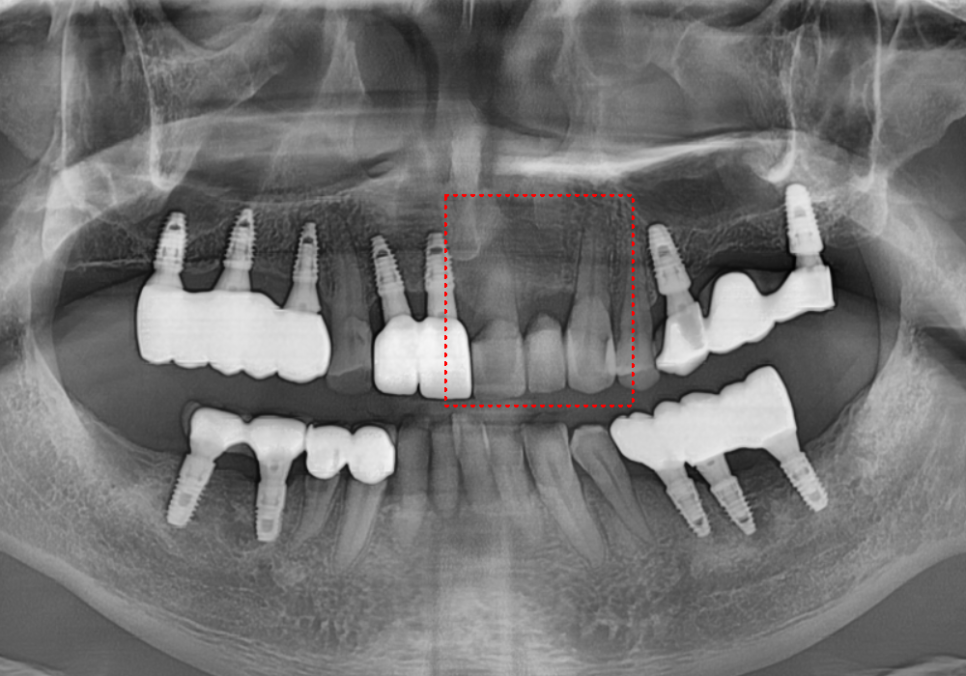

이 환자분은 오래전에

왼쪽 앞니부터 송곳니까지(#21~23)

치아 3개를 연결한

'브릿지' 치료를 받으셨다고 해요.

불편해하시는 부위를 자세히 살펴보니,

문제의 발단은

브릿지 끝 치아(#21)와

그 옆에 있는 임플란트(#11) 사이였습니다.

이 틈으로 계속 음식물이 꼈는데,

방치하다 보니 결국

심한 통증으로 이어진 것이죠.

엑스레이로 확인해 보니

역시나 예상이 맞았습니다.

230516

앞니 옆면을 타고 뿌리 깊숙이

충치가 까맣게 진행 중이었습니다.

원인은 바로

'제거되지 않은 음식물'이었는데요.

브릿지 틈새에 낀 음식물이

빠지지 않고 안에서 부패하면서,

보철물 속의 치아를

야금야금 녹이고 있었던 겁니다.